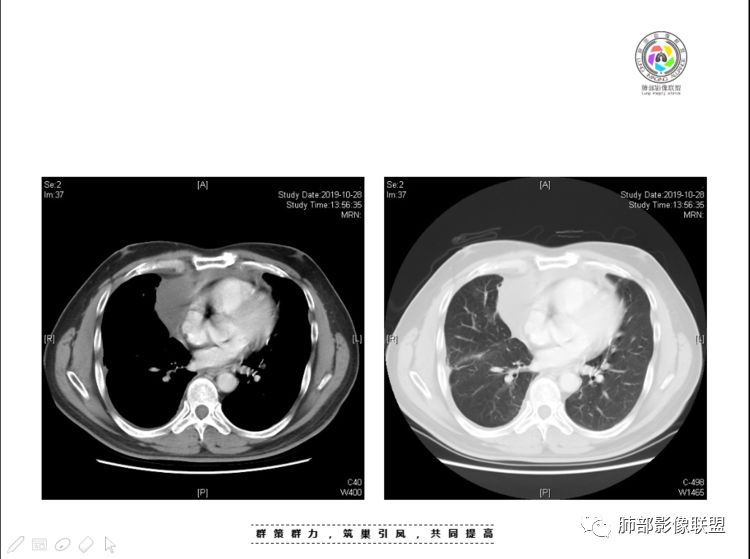

2、前纵隔内病灶囊实性混杂密度病灶,囊性病灶主要位于右侧,张力较高,有分隔影,囊壁右侧缘光整,病灶左侧实性部分边界不清明显强化,病灶肺瘤交界面大部分边界清楚,部分模糊。

前纵隔肿块伴囊变坏死常见以有胸腺瘤、胸腺癌、淋巴瘤和生殖细胞肿瘤。

纵隔内病灶不符合肺癌转移途径,且纵隔内单发的囊实性转移罕见。淋巴瘤无论是分布、形态、密度、还是强化方式度不符合。

胸腺瘤/胸腺癌符合吗?

胸腺瘤/胸腺癌:病灶内那么大的囊,常规考虑B型以上胸腺瘤,囊内有分隔影,病灶周围脂肪间隙模糊,常规考虑侵袭性胸腺瘤或胸腺癌,若侵袭性胸腺瘤,常侵犯胸膜、心包,很少累及肺。胸腺癌易侵犯胸膜、肺并纵隔淋巴结及远处转移。但肺内腺癌形态更符合原发灶。胸膜及叶间裂转移则即可来自肺,也可来自胸腺癌。